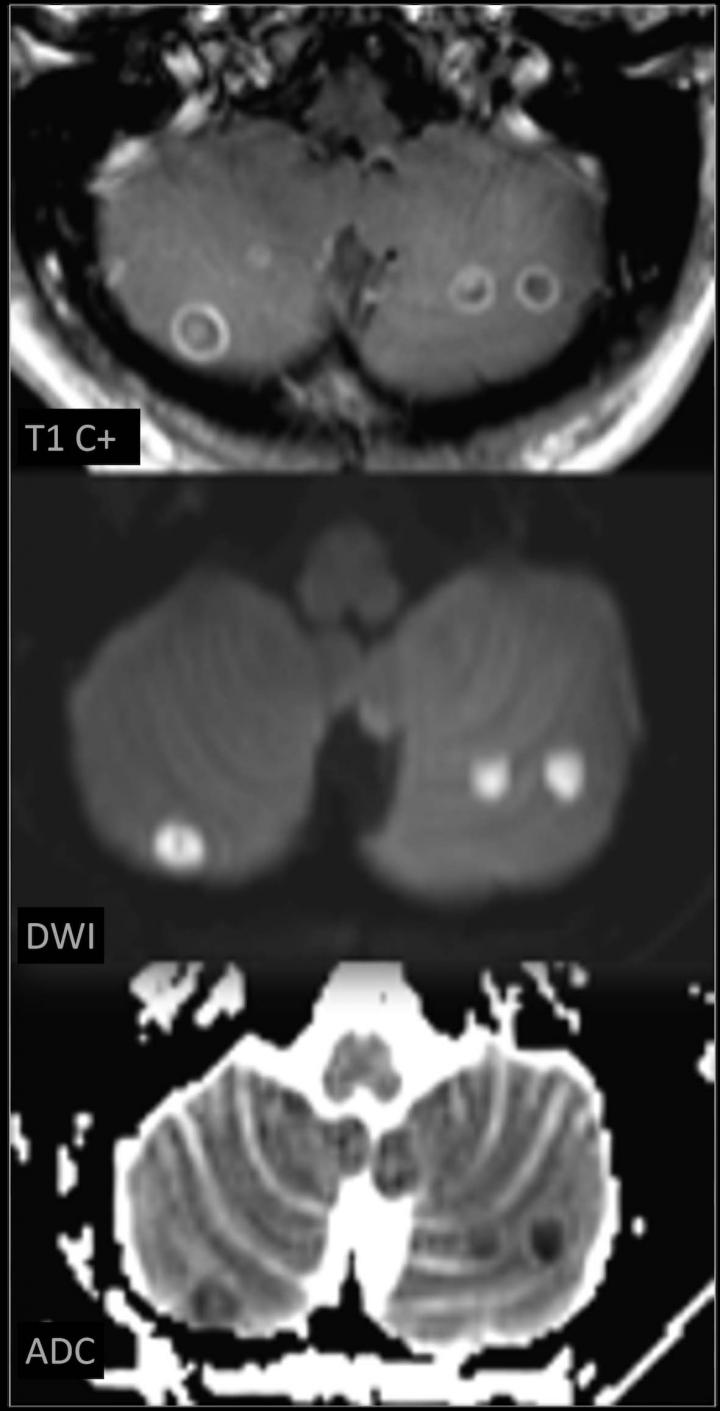

"Complications were most frequently related to skin and soft tissue infections caused by the use of non-sterile needles," Dr Flores said. "In some cases, we found septic emboli in the lung or brain. As these patients start having to access larger veins, they become more prone to these types of infections."

There were 1,673 imaging exams performed, including 779 X-rays, 544 CTs, 292 MRIs and 58 ultrasounds. Imaging results often provided critical information, such as when physicians changed the management plan for a patient with a substance-abuse-related lumbar spine infection after CT scans showed the involved nerves.